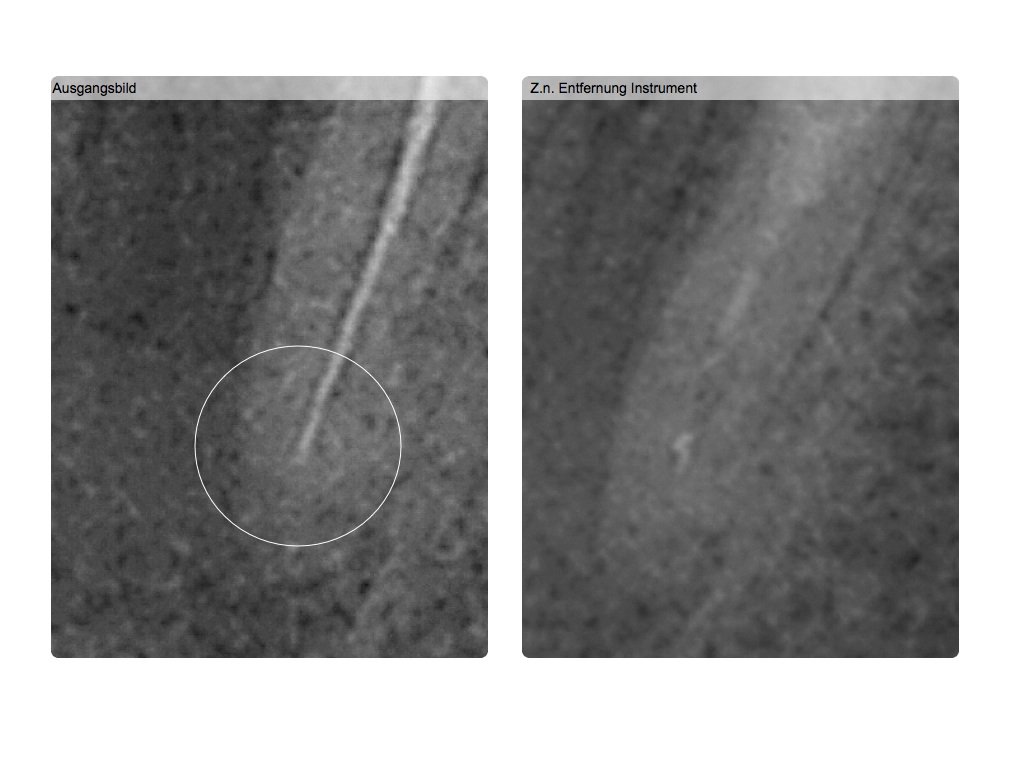

Röntgenbilder lügen…